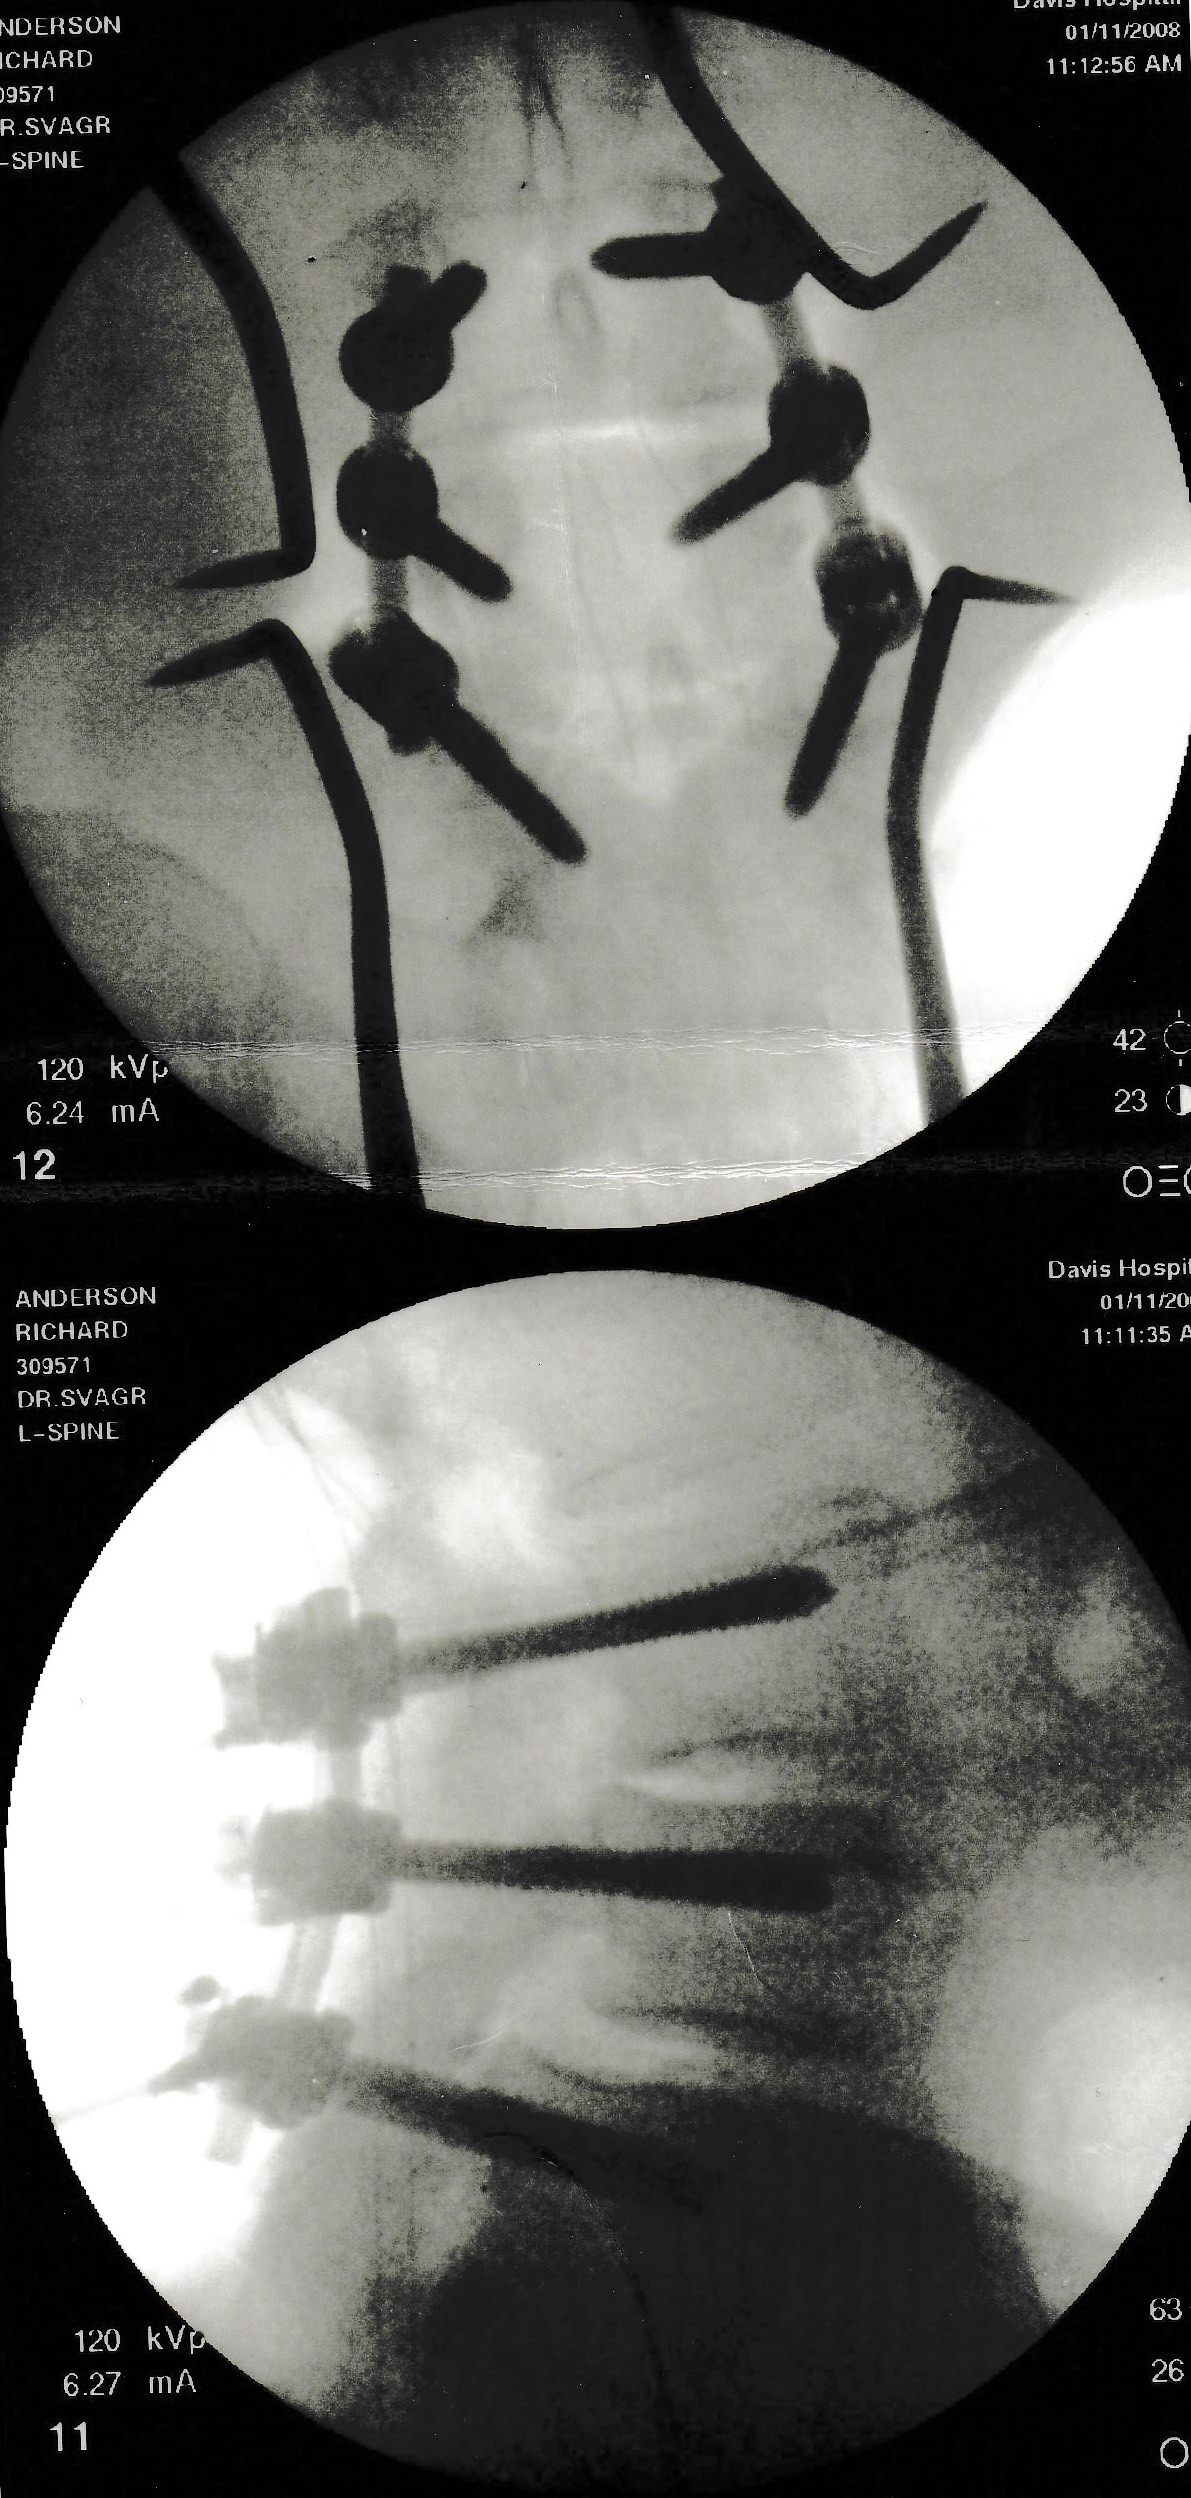

2008—Lumbar fusion |

On January 11, Dr Svagr performed a lumbar fusion, bolting together three levels of vertebrae and cleaning out accumulated débris from my lifelong tendency to spondylolysis. |